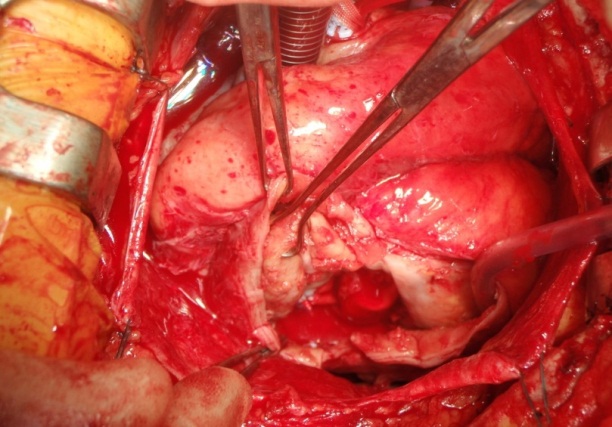

Figure 2: Organised thrombus removed from aneurysmal sac.

The patient underwent left ventricular aneurysmectomy. Standard median sternotomy was used and the patient was placed onto cardiopulmonary bypass via a two stage venous cannula in the right atrium. An aortic clamp was applied and cold blood cardioplegia was infused into the aortic root. With the heart arrested, the inferior aneurysm was dissected and opened, and approximately 250 grams of thrombus was removed. The neck of the aneurysm was demarcated (30 mm wide by 50 mm long), and was oversewn with a sauvage Dacron patch using 2.0 prolene (Figure 3). This was reinforced with Teflon pledgeted 3.0 prolene interrupted sutures. The remaining aneurysm sac was removed and closed with Teflon to buttress over the patch with a 1.0 Prolene Carrel stitch.